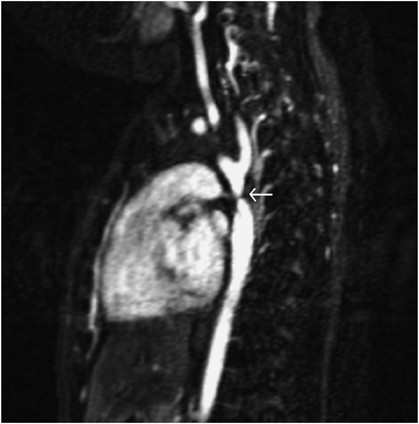

Figure 1

Contrast magnetic resonance image in the sagittal plane demonstrating the heart anteriorly and descending aortic arch and descending aorta posteriorly. Discrete coarctation of the aorta is indicated by the white arrow after the origin left subclavian artery. Numerous prominent collateral arteries providing collateral flow are seen.